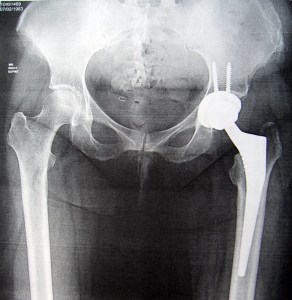

I saw my doctor, Bryan Springer, MD of OrthoCarolina, exactly one month after my surgery. The first thing he said was when he did the surgery my hip looked pretty bad in there, then he showed me my x-ray of my new hip, and said I was doing great! I go back to see him in 3 months! Woo Hoo! I did request to go to further physical therapy since I didn’t get to finish my PT at home and he was all for it. Unfortunately, I haven’t been able to start it yet. I’ll be doing Aquatic Therapy and the place I went before have drastically cut their hours so I’ll be going to a different place. I’m a little nervous because the other place was very quiet and I could easily hear my therapist. I don’t know how the new place will be, I have a LOT of trouble with my hearing so if it is the slightest bit noisy in there I may have a lot of difficulty.